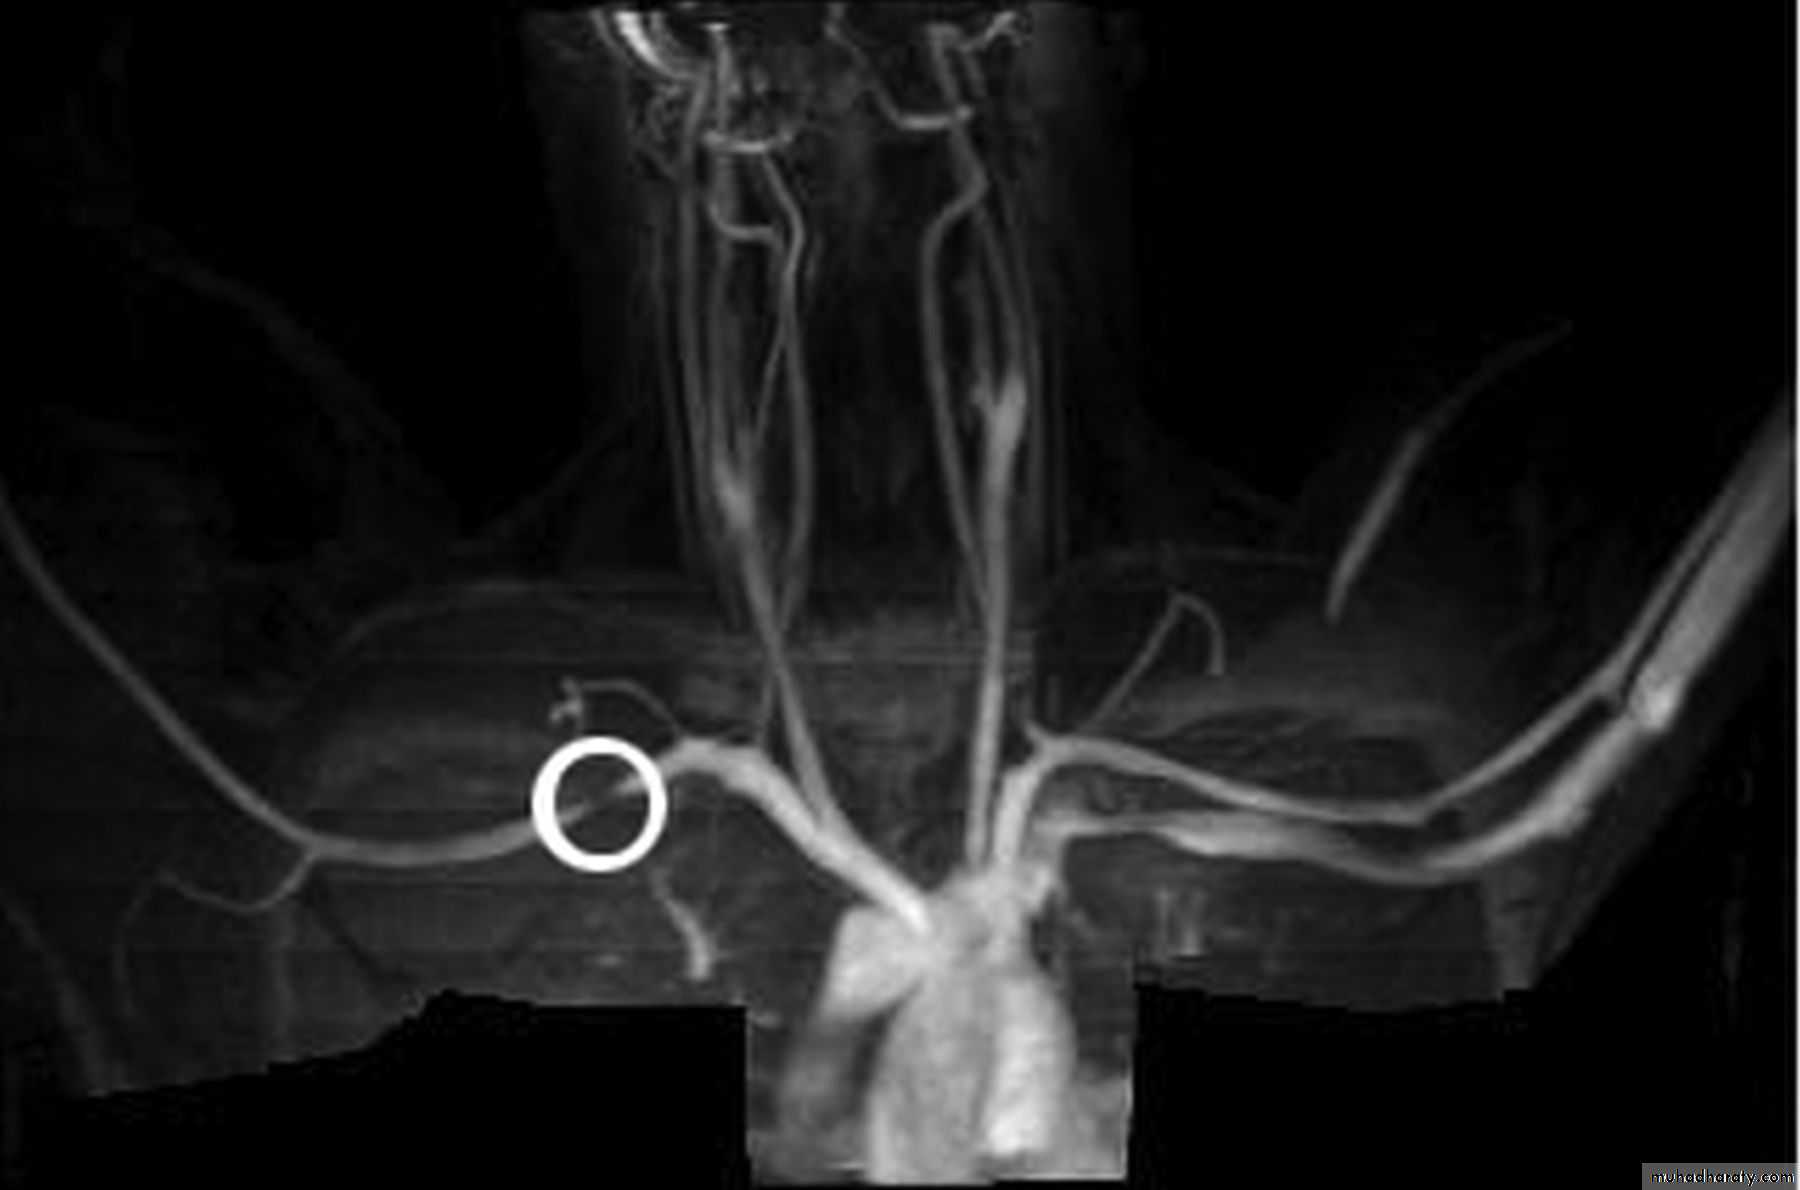

Angiography

MRI & MRA